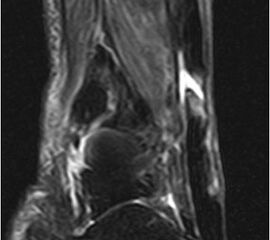

Der geübte Untersucher kann anhand des seitlichen Röntgenbildes die Diagnose einer Achillessehnenruptur stellen. Die Konturen des Kager-Dreiecks – gebildet von der ventralen Begrenzung der Achillessehne, der posterioren Tibiakante und der kranialen Kalkaneuskortikalis – verstreichen im Rupturfall (Kager 1939). Die MRT- Diagnostik spielt für die Primärdiagnostik der frischen Achillessehnenruptur eine untergeordnete Rolle und ist im Normalfall nicht notwendig. Anders verhält es sich bei den chronischen Rupturen. Hier ist die MRT ein wichtiges Diagnostikum insbesondere in Hinblick auf die Beurteilung der Sehnen- und Muskeldegeneration (Abb. 6).

Abbildung 6

Neben der strukturellen Wiederherstellung der Sehne ist die funktionelle Beurteilung des Muskels von entscheidender Bedeutung. Ist es bereits zu einer Degeneration der Muskeln gekommen, kann ein gutes funktionelles Ergebnis, trotz subtiler Sehnenrekonstruktion, nicht erreicht werden. Die Arbeitsgruppe um Hoffmann et al. 13 konnte in ihrer Arbeit zeigen, das es - ähnlich wie bei Patienten mit chronischen Supraspinatusrupturen - zu fettigen Degenerationen und Ödemen der Muskulatur kommt, die im MRT nachweisbar sind. Wir empfehlen die MRT- Untersuchung des gesamten Unterschenkels und nicht nur die rupturnahen Bereiche. Des Weiteren lässt die MRT eine Beurteilung der Degeneration der umliegenden Sehnenanteile zu. Die Computertomographie sollte nur in Ausnahmefällen zum Ausschluss von Begleitverletzungen (Abb. 7) durchgeführt werden und gibt uns sonst keinen weiteren Informationsgewinn.